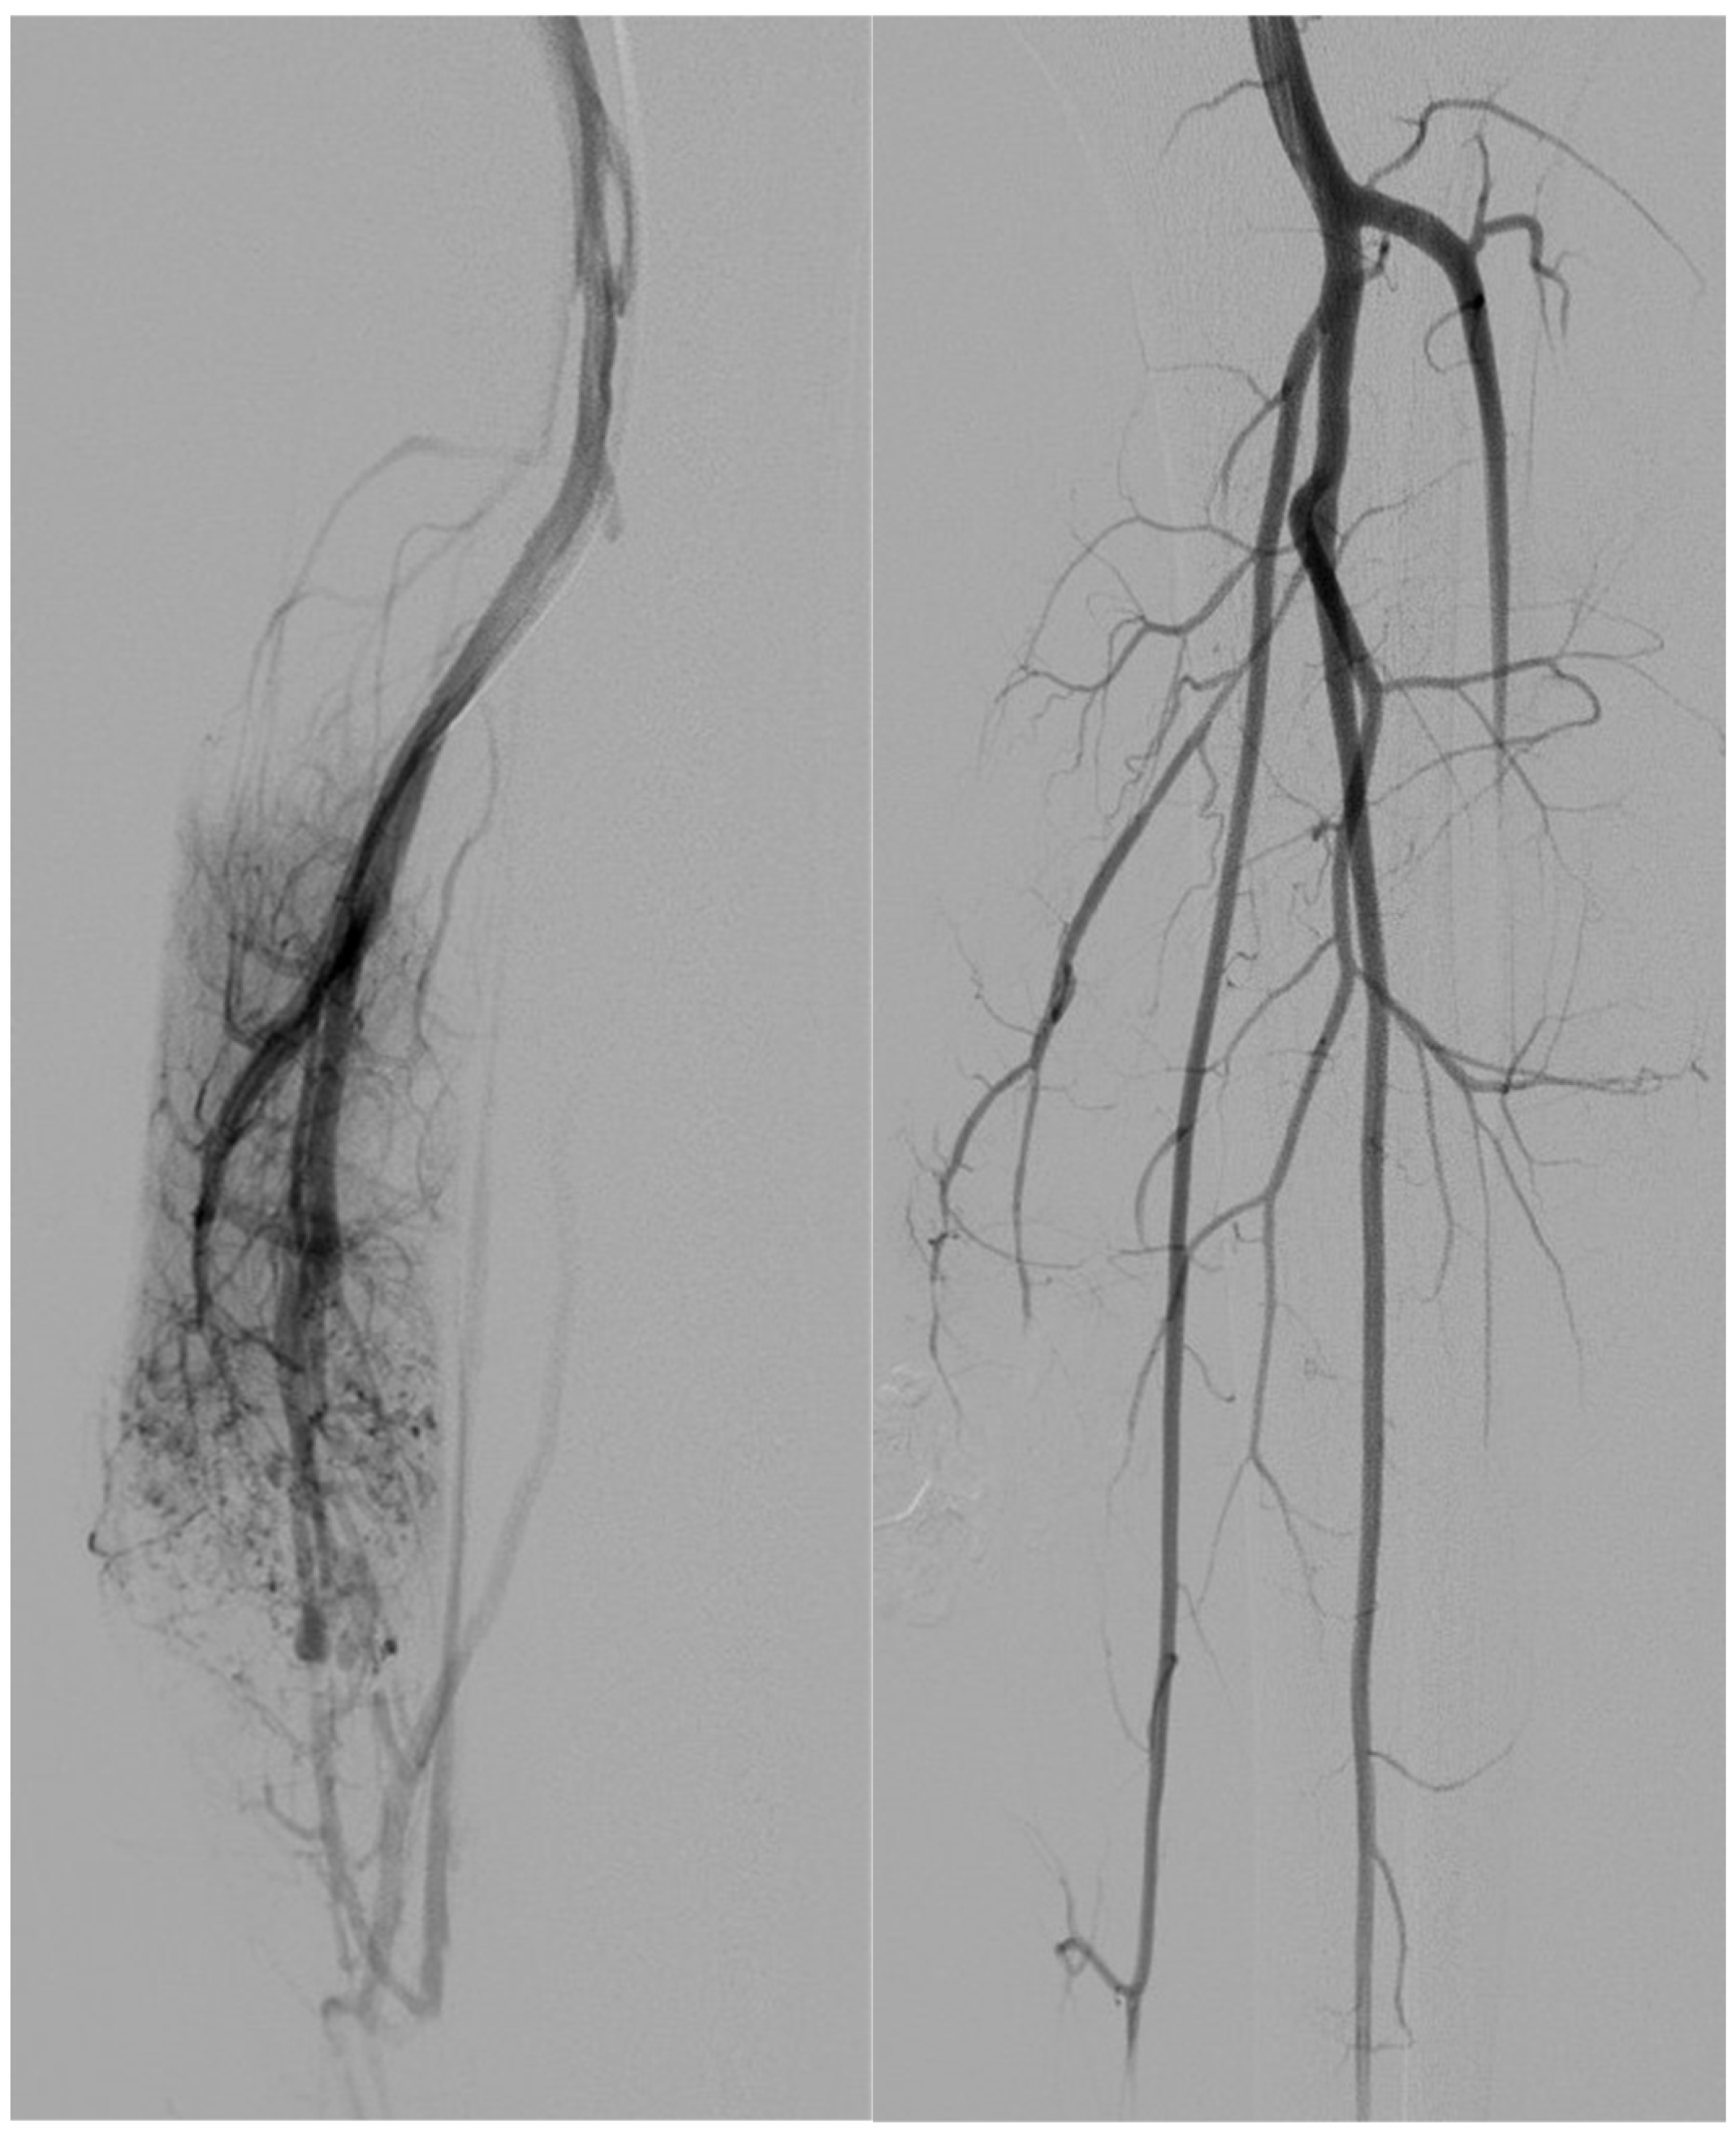

- Arterial embolization was preferred in lesions with limited and accessible feeders.

- Venous embolization was favored when the dominant outflow vein (DOV) was accessible and formed the site of arteriovenous shunting.

- Combined arterial and venous embolization was used in complex lesions with multilevel shunting, high-flow recurrence, or partial response to single-route embolization.